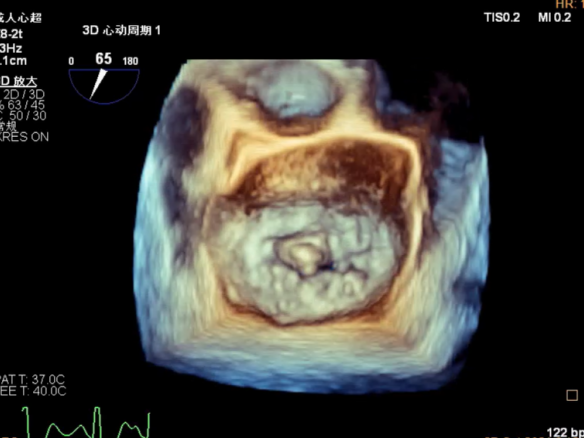

确定房间隔穿刺点:略靠前,3D视图2点位

穿刺点高度测量:4.37cm

Multivue测量大鞘长度2.34cm

3D视图下观察二尖瓣双孔形态

3D-color:残余少量返流